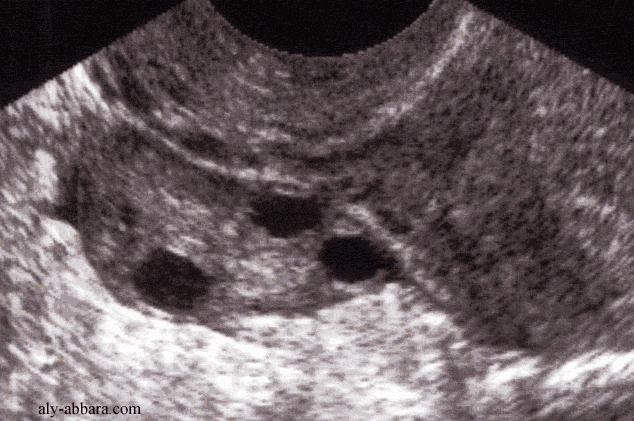

Aspect échographique d'un ovaire droit normal

chez une femme âgée de 32 ans